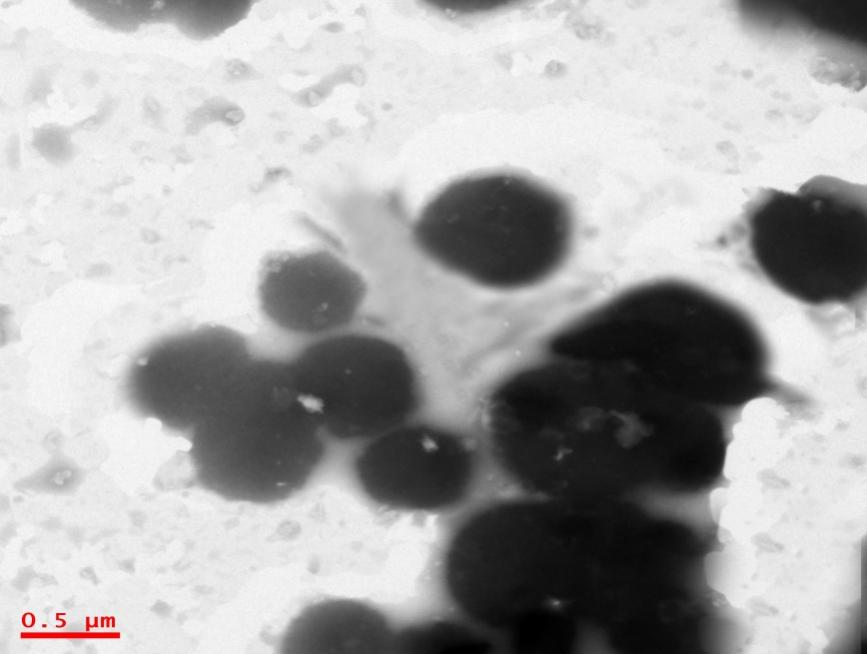

Morphology of agomelatine

The TEM indicates the morphology of vesicles, and the TEM images for AMN3 were found to be spherical with a uniform surface. The vesicles were spherical with very flawless borders. The uniform surface and shape of vesicles have proved that there won't be any drug leakage happening from the formulations.

Fig. 1: Morphology of agomelatine ethosomal vesicles (x 500)